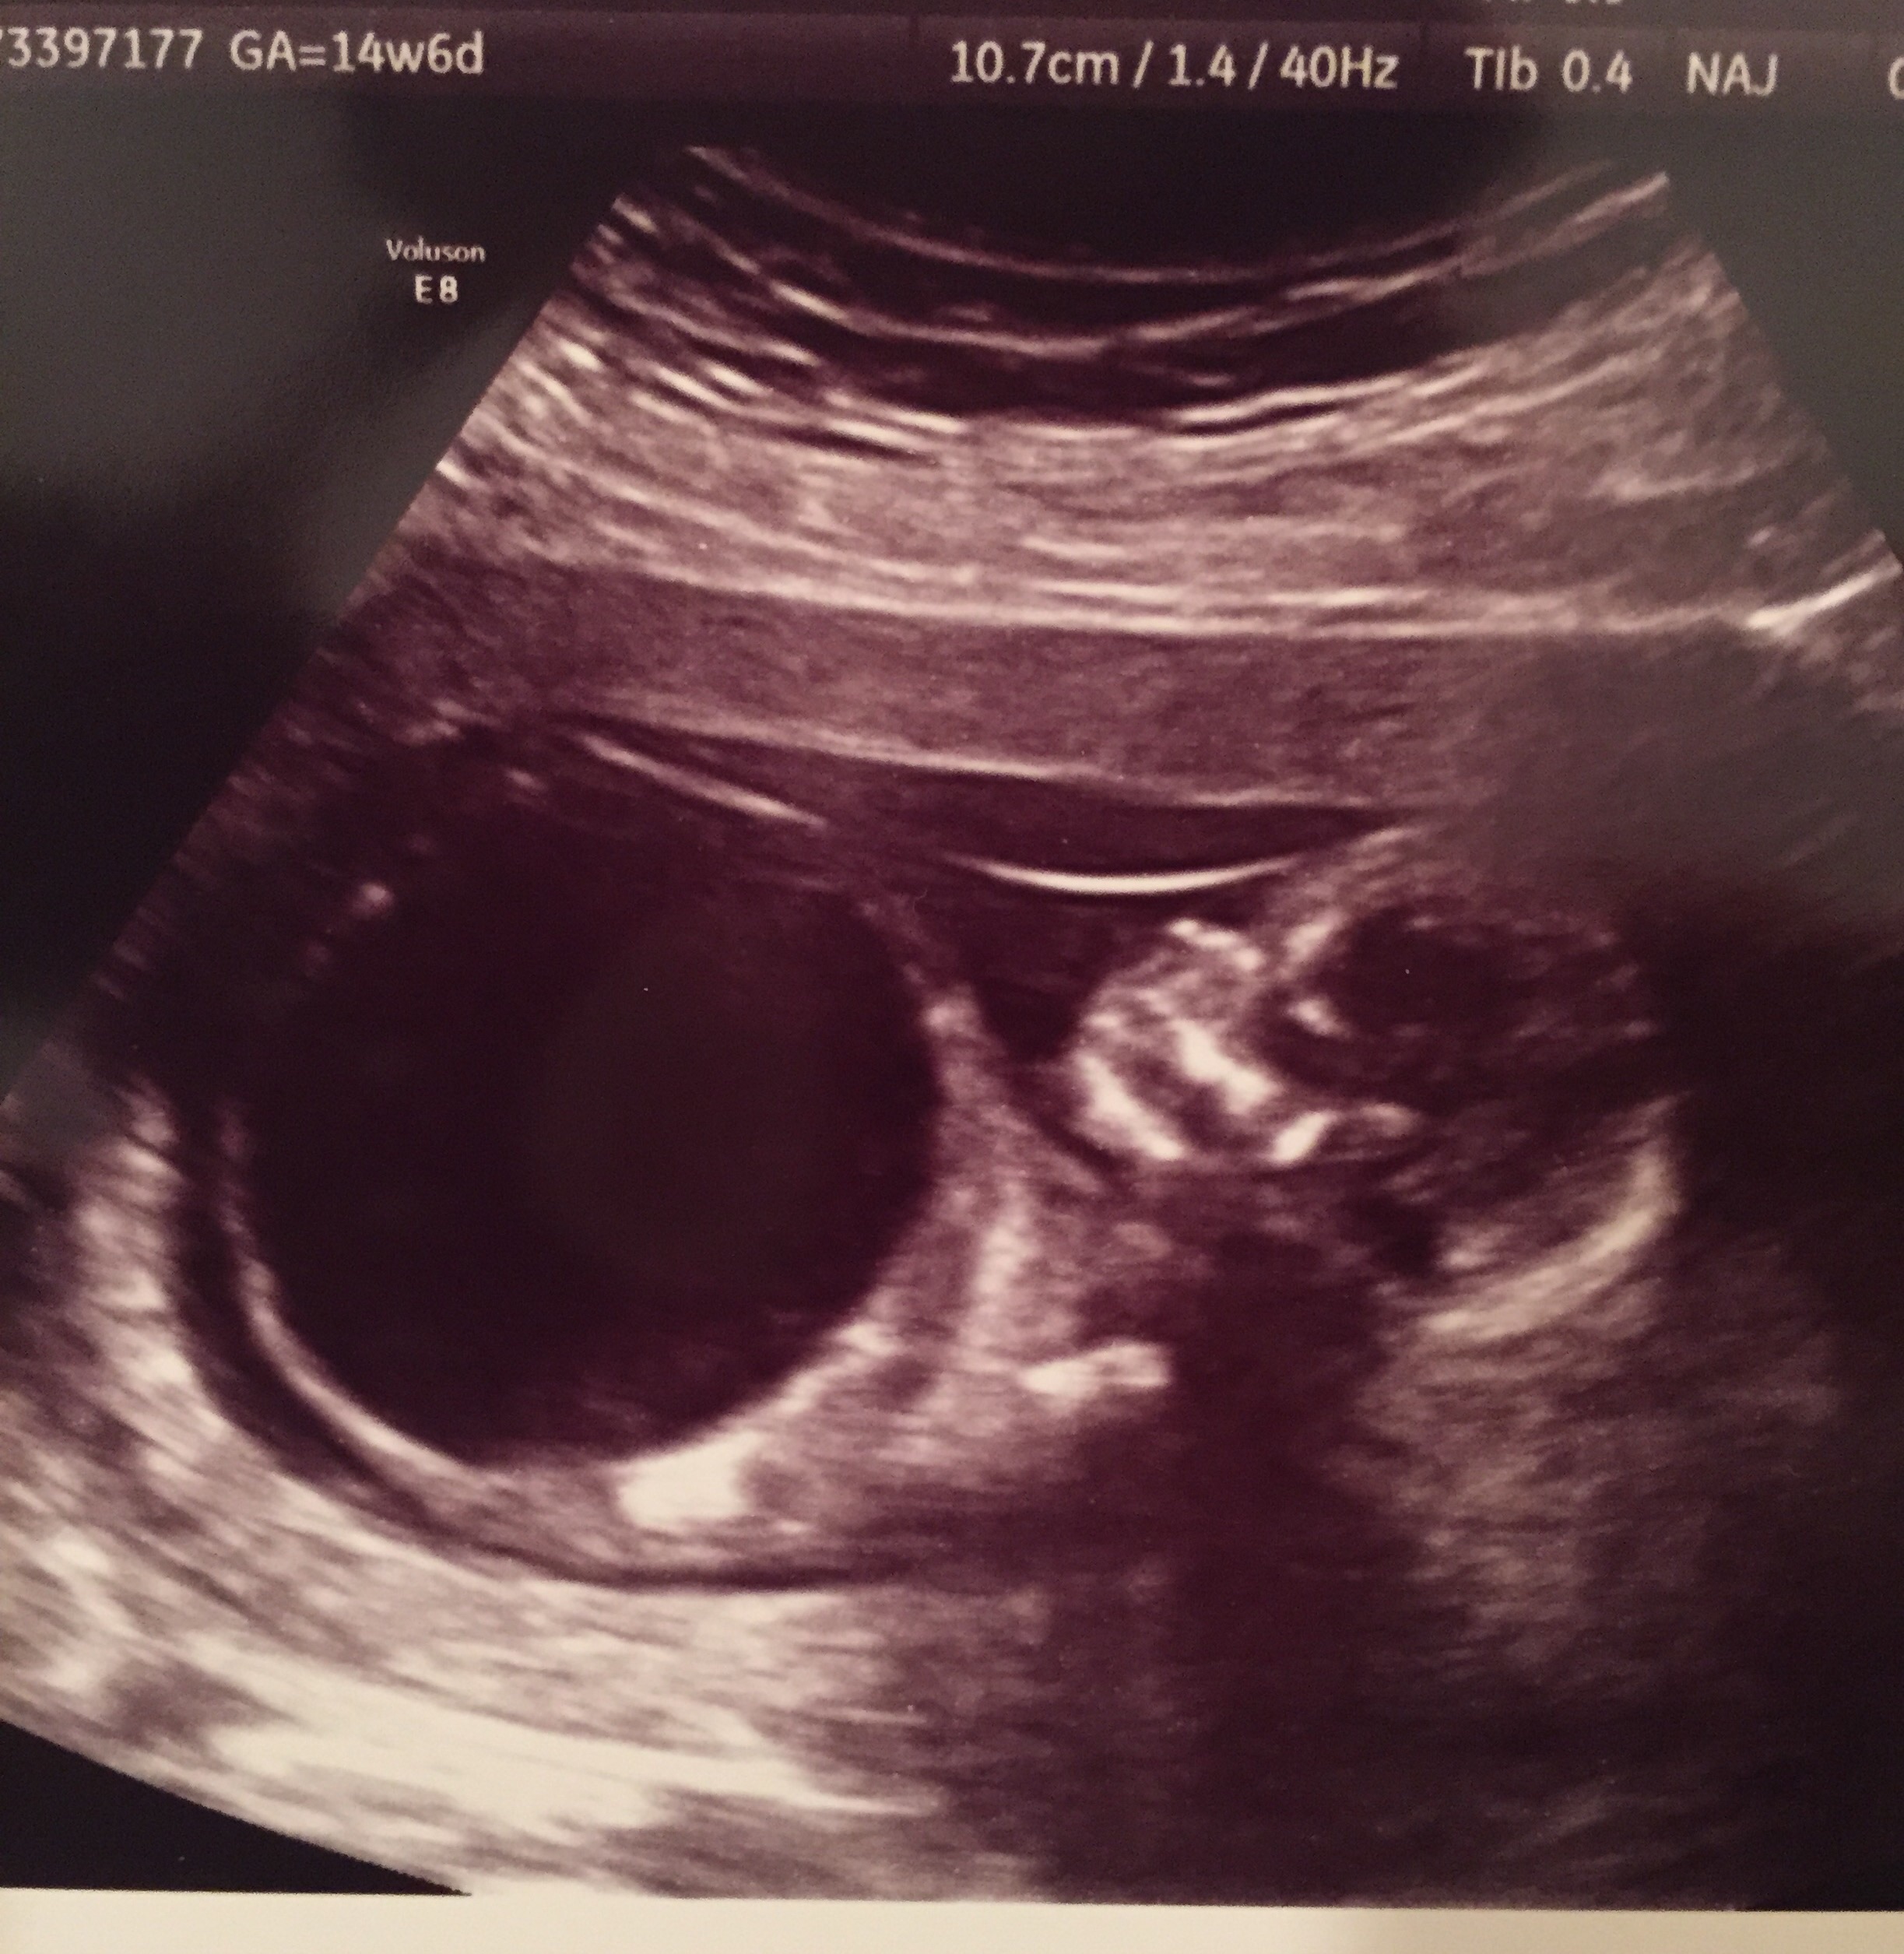

At my 14 week appt the doctor decided to do an ultrasound which wasn't planned until week 22! Thank God that she did because they found that my little guy has a bladder outlet obstruction! We are being sent to the Cincinnati fetal center next week to see several specialist! They said that we caught it early which is a good thing! But they are either going to have to put in a stint to drain the babies bladder into the amniotic fluid and do corrective surgery after he is born or they will do corrective surgery in-vitro if the kidneys are healthy enough! We would appreciate all the prayers and positive thoughts you lovely ladies could send our way! I know God has this but would love to have you all standing in faith with me!